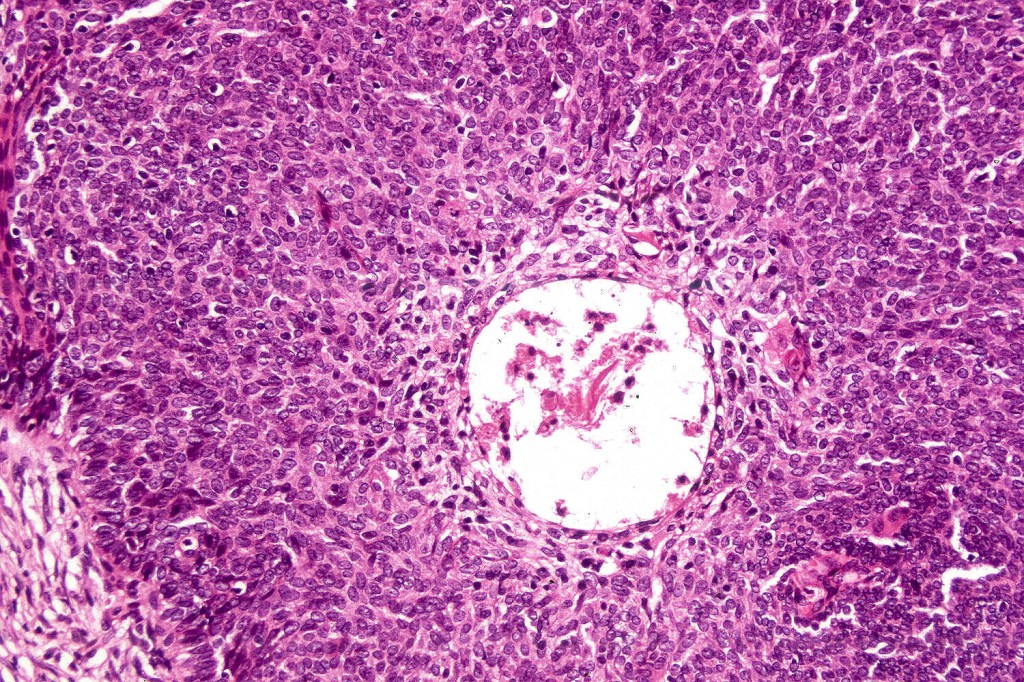

•Trichogerminoma is a distinctive variant being composed of tumor nodules with basaloid cells surrounding pale or eosinophilic micronodules (Zellballen)